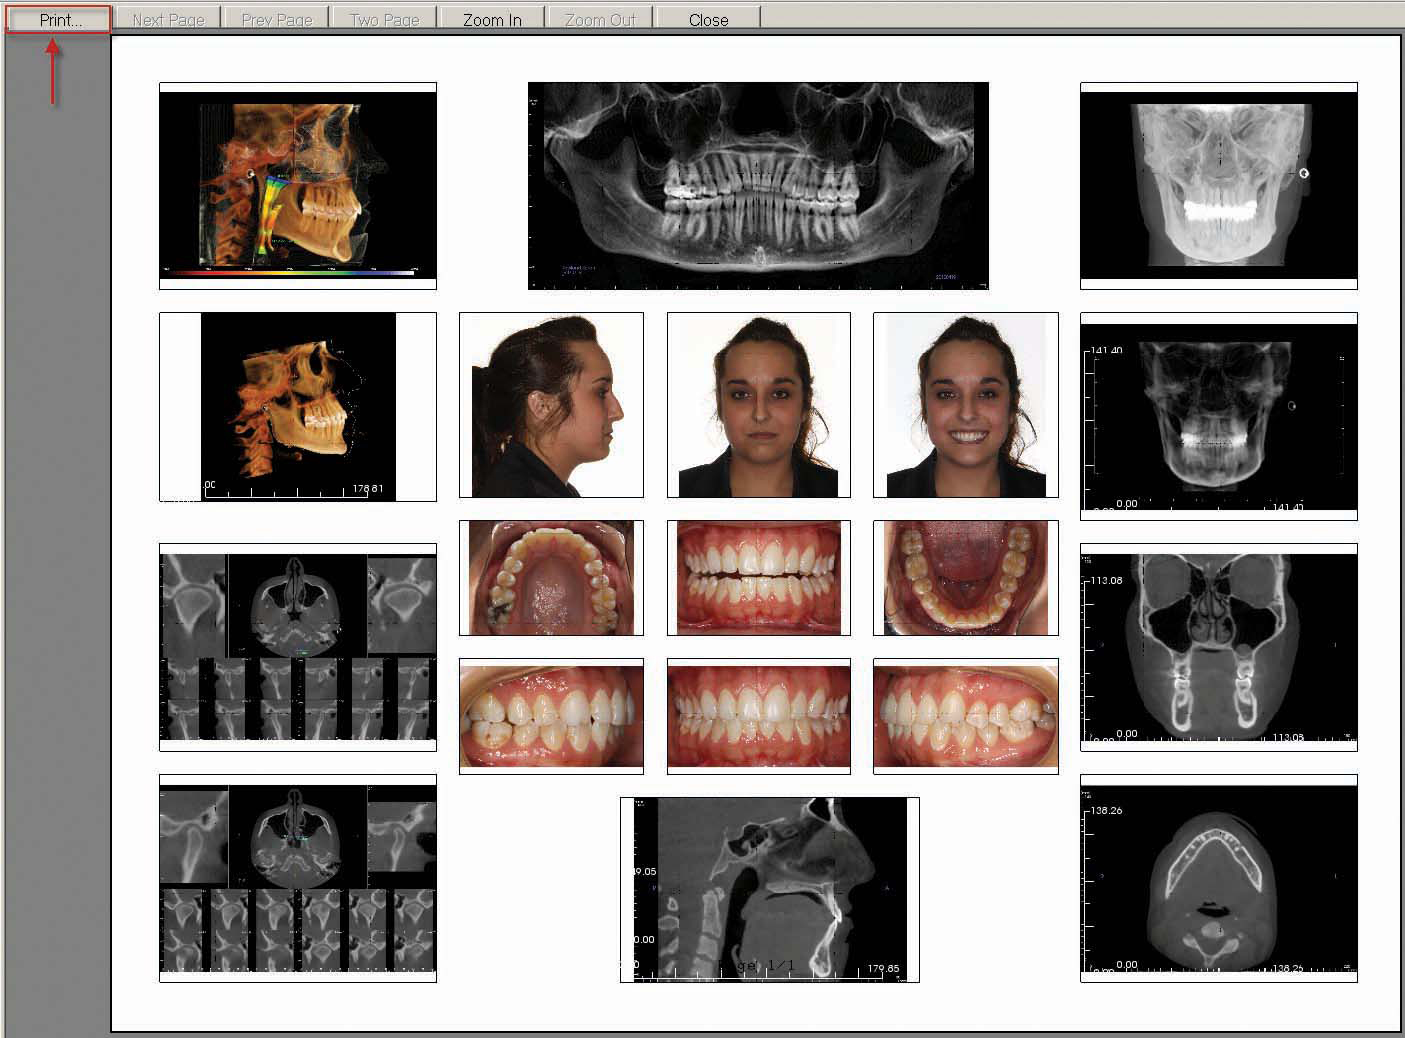

8) The German template is complete! Click on the report tab to view the populated template.

If any images are missing, ensure that the spelling and case of the image title are identical to the template label, then resave the missing image(s) to "Capture to Gallery" to automatically populate the template.

9) In order to print the template, go to "File" and select "Print Setup." Be certain that "Landscape" orientation is selected, and then click "OK." Next, return to the "File" menu and select "Print Preview." If the image shown is correct, click "Print" and then "OK."

10) The template can also be saved as a .jpeg, .bmp or .png file by going to "View" and selecting "Capture to File" from the drop-down menu. Enter a "File name" and select the desired file type from the "Save as type" drop-down menu, then click "Save."